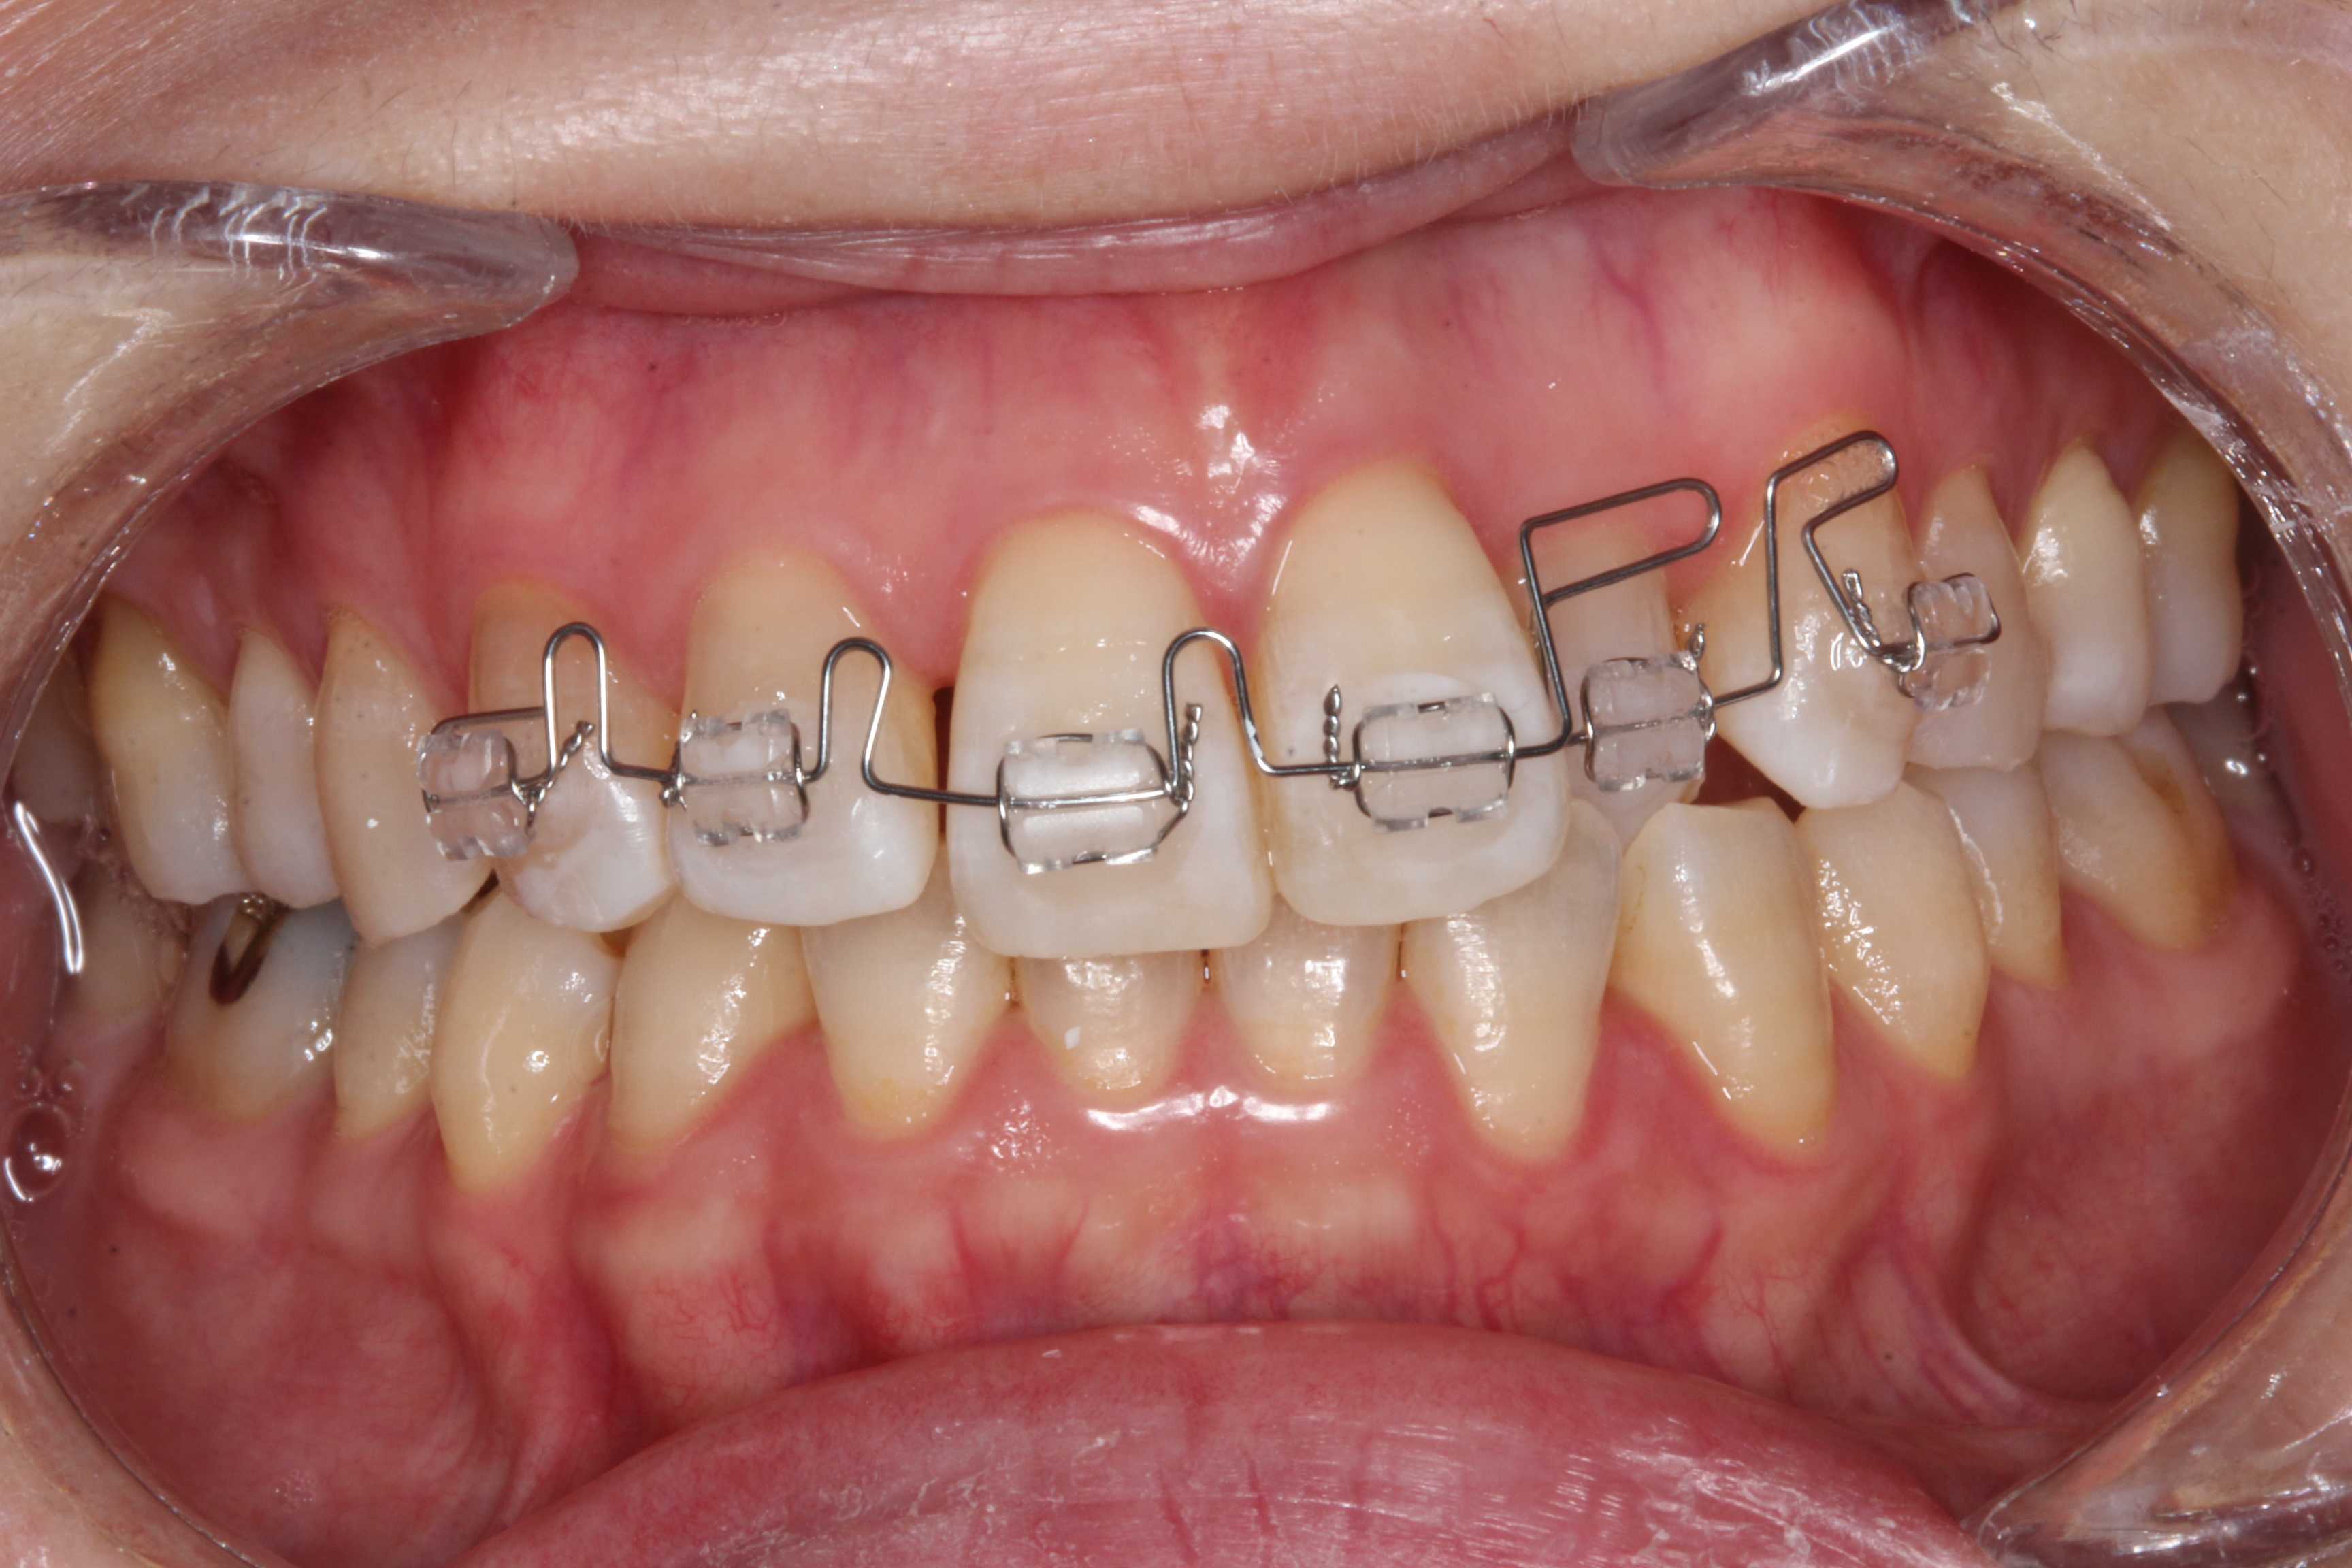

12歳女子、左下7、すれ違い咬合この時のつづきを例にとって、臼歯部のブラケットは何を選べばいいの?というお話。これは部分矯正なのだけれど、全顎ブラケット&ワイヤー矯正でも同じです。https://plaza.rakuten.co.jp/mabo400dc/diary/202508040000/before/afterからbefore2025/04/26起きてくるまでは上顎にこの部分を抜いたスプリントを入れます。起きる時に上顎に干渉して起きませんので。レベリングワイヤーは丸の014"動かす必要のない6543は連結固定してアンカーとして使います。このアンカーという考え方は歯列矯正治療には重要な考え方で、常に考えておかないと上手くいきません。特定の歯を動かすということはそれ以外の歯が反対方向に動くということです。作用反作用の関係で動かすということです。ですから、動かしたくない歯はなるべく多い方が良いアンカーになるということです。良いアンカーがない時はネジを顎の骨にねじ込んで使うのですが、それをアンカースクリューと言います。しかし、作用反作用をよく考えれば不要なケースが大半です。アンカーが動きすぎたら戻す、それを繰り返しながら収束させるという考え方です。after2025/08/26ブラケットが干渉するときは壊れない程度に削って良いです。レベリングが終わったら角ワイヤーに換えます。細い角ワイヤーは016"-016"(オーワンシックスーオーワンシックス)しか入手できなくなった。7番はバッカルチューブ.018"、6番は大臼歯用のメタルブラケット.022"、小臼歯は.018"のメタルブラケット。これだけでOK。このまま歯科材料屋さんに見せて発注してください。咬合の中心(最初に当たる)は6番ではなく小臼歯なので、ここは018"(オーワンエイト)でしっかりワイヤーを固定した方が良い。6番はスロットは狭いほど調整が難しいので広めの022"(オーツーツー)のメタルブラケットで楽をしましょう。態癖(寝相等)の対策をすればバンド冠など全く必要ありません。7番はトルクを強く掛けるので018"で。矯正治療のノウハウに関するシリーズはこれで終了です。直近の「今日の歯列矯正シリーズ」6記事を参照してください。これだけで良いのです。後は自分の頭で考えて実践するだけ。

40代女性、左上2、クロスバイト前回のつづきhttps://plaza.rakuten.co.jp/mabo400dc/diary/202509290000/ブラケットワイヤー装着から3ヶ月ほどで改善する、その後は患者の細かい要望に応じたりしながら微調整と保定に入る準備をする。いきなりブラケット&ワイヤーを除去することはできない。歯槽骨が動かした直後はゆるゆるなので、どうなるか分からない。後戻りしたり、思いっきり歯列が歪んだりする。最低でも2年くらいは用心しないと悲惨なことになる。2025/04/01拡大症装置を2年程使って十分広がって、動かすスペースができたのでブラケット&ワイヤーを装着した。最初はレベリングと言ってブラケットのスロット(ワイヤーの入る溝)を一列にする工程。ワイヤーは丸014"左右の3456は動かす必要はないので、スーパーボンドで歯列固定している。奥歯全部をアンカーに使えるし、患者も術者も楽だ。歯列狭窄が元に戻らないように床装置は入れている。https://plaza.rakuten.co.jp/mabo400dc/diary/202509260000/2025/04/26隙間をパワーチェインで引っ張って寄せる2025/05/20左上2番の先が引っかかっているので、太めの丸ワイヤー016"に交換した。2025/06/18被蓋は改善したので微調整に入る。動かす必要のないところは連続結紮しておく。角ワイヤーの016"-016"2025/08/26床装置はそのまま保定装置として使える。

40代女性、左上2、クロスバイト前回のつづきhttps://plaza.rakuten.co.jp/mabo400dc/diary/202509270001/ブラケット装着とワイヤーベンディングとは言え、こればかりは教科書どおりでいいです。画期的な手抜き方法があるわけではありません。理想的な歯並びというのもあるような無いようなというのが現実で、その子に合わせてアレンジします。理想的な歯並びというのは矯正歯科医の頭の中だけにあるイマジナリーなもので、絶対的なものではありません。一般的には下図のようなもので、アーチ自体の形は丸ワイヤーも角ワイヤーも同じです。角ワイヤーを使うときはトルクと言って歯軸の傾斜を付ける必要があります。これは大御所の先生によっても違いますので、ここにある数字の中間位を目指します。特にブラケット装着は出来上がりの姿を想像しながらしないと後で困ります。1つだけ低いとか曲がっているとかがあるとワイヤーをそこだけブラケットに合わせて曲げないといけなくなるので面倒です。ブラケット装着は最初が肝心!全顎ブラケット症例も部分矯正も基本同じです。矯正用の道具はこれだけでOKです。ローレットとか初心の頃は使うこともありましたが、面倒なだけです。結紮線を使うことには慣れるしかないです。ホーのプライヤーでくるくる回して締める練習をしてください。パワーチェインとオープンコイルスプリングブラケット装着用のピンセットとブラケット除去用の鉗子。これだけでOKで、学生実習で購入した器具に少し買い足すだけで十分でしょう。つづく

40代女性、左上2、クロスバイトhttps://plaza.rakuten.co.jp/mabo400dc/diary/202509260000/今日はブラケット&ワイヤーの選定ということで具体的なお話です。歯学部を出ただけでは矯正治療など全くできないということに気が付いて愕然とするのだけれど、大学院などに行くお金もないし、お高いセミナーに出かけるお金も時間もない、という諸兄に朗報です。最近はアンカースクリューを使った矯正とか、色々な方法が歯科矯正業界には溢れているのだけれど、実はそんなのはなくても大丈夫なのです。ここでご紹介する方法や材料は非常にシンプルなので導入しやすいと思います。僕も昔は色々器具や材料を集めていましたが、今はシンプルです。ブラケットは各歯牙に基本1種類、ワイヤーは4種類でOKです。道具も4種類だけ。これは後程画像をアップしましょう。矯正治療を始めようと思っても、機材のカタログは分厚く、その中のどの製品を選べば良いか分からないという高い壁があります。多くの矯正治療を志す歯科医師はこの最初の段階で挫折します。その壁をあっさり崩そうというのがこの記事の趣旨で、これだけでOKという話です。ではここで使っているブラケットから3〜3は透明のプラステックのブラケットを使います。ま、見た目です。スロット幅は.018(オーワンエイト)というものです。この手の呼称は業界用語です。歯科材料屋さんに下の画像を見せて発注してください。下顎の3〜3も同じ透明のシリーズがありますが、被蓋が深くて上顎前歯の舌側と干渉する時は小さめのメタルブラケットを使う時もあります。それらがこれ下顎前歯部用ブラケット。小さめのメタルブラケットはスロット幅.022(オーツーツー)。広い方がワイヤーベンディングが簡単だし、患者も痛くない。ワイヤーは丸ワイヤーの.014(オーワンフォー)という1番細いものです。Uループ、Ωループ、Lループ、Tループ等は使い分けます。オープンコイルスプリング、パワーチェインは必要に応じて使います。部分矯正の断端の処理法を見ておいてください。オリジナルです。動かす必要がない臼歯部はスーパーボンドで歯間部を連結固定しています。これでめんどくささ激減。患者負担も最小限。その他には丸の.016、角ワイヤー.016-.016(オーワンシックスーオーワンシックス)、たまに.016-.022(オーワンシックスーオーツーツー)を使うことも。というか、販売中止になってしまった.016-.018(オーワンシックスーオーワンエイト)があればこれ一本で済んだのですが。。硬さはミディアムでOK.今どんどんワイヤーの種類が減っています。世界的にブラケット&ワイヤーを使う歯医者が減っているのかもしれません。マウスピース矯正に押されている?マウスピース矯正ではできない症例も多々あるのですが。実はもっと太いワイヤーも使うのが一般的なのですが、細いワイヤーだけで並びます。太いワイヤーが必要な訳は、実は矯正専門医も気にしていないというのか、知らないのか、長く通わせるための大人の事情があるのか分かりませんが、寝相(態癖)対策なのです。うつ伏せ寝、横向き寝、頬杖等で矯正治療中の歯はゆるゆるなので動きやすいく、思いっきり歯列が歪んだりします。それを抑えるには太いワイヤーが必要になるということです。舌側弧線も同じだと思って良いです。態癖の対策は別途行えば太いワイヤーは使わずに済むので、術者も患者も楽です。上顎前歯部用の透明ブラケットはこれだけでOKつづく